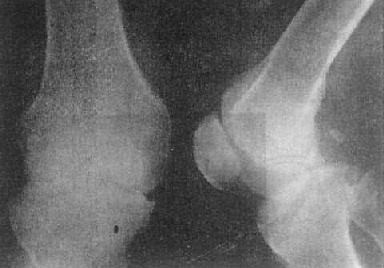

关节破坏——膝关节结核

图2-1-14 关节破坏——膝关节结核

膝关节关节间隙变窄,关节面边缘有虫蚀状骨破坏